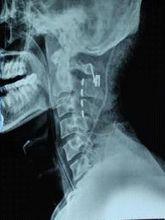

昏迷促醒圖為植入後的X線片,可見植入到高頸段的點狀電極